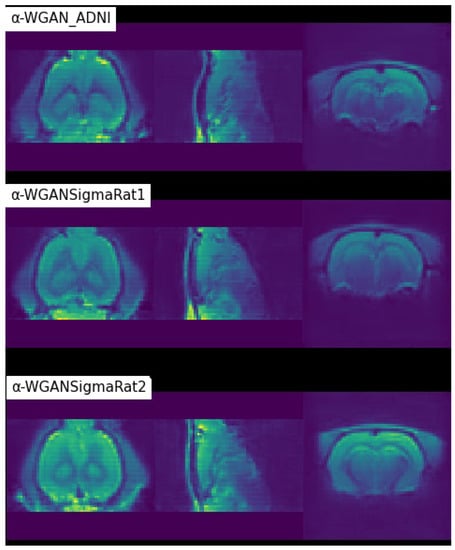

| -WGAN_ADNI [26] | 0.6860 | 0.7241 | 0.0316 | 779.4653 |

| ±0.0066 | ±0.0071 | ±0.0004 | ±27.2016 | |

| -WGANSigmaRat1 | 0.8118 | 0.7887 | 0.0305 | 753.1584 |

| ±0.0051 | ±0.0041 | ±0.0004 | ±24.8816 | |

| -WGANSigmaRat2 | 0.8236 | 0.7527 | 0.0325 | 819.3409 |

| ±0.0056 | ±0.0037 | ±0.0003 | ±20.4437 |